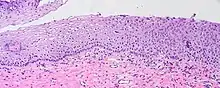

Koilocytes can be visualized microscopically when tissue is collected, fixed, and stained. Though koilocytes can be found in lesions in a number of locations, cervical cytology samples, commonly known as Pap smears, frequently contain koilocytes.[5] In order to visualize koilocytes collected from the cervix, the tissue is stained with the Papanicolaou stain.[5] Another way koilocytes can be visualized is by fixation of tissue with formalin and staining with hematoxylin and eosin, commonly known as H&E.[5] These stains give the cytoplasm and nuclei of cells characteristic colors and allows for visualization of the nuclear enlargement and irregularity, hyperchromasia, and perinuclear halo that are typical of koilocytes.

In LSIL of the cervix, definitive koilocytes are present. In addition, squamous cells commonly display binucleation and mitoses are present, signifying increased cellular division.[7] However, these changes are primarily limited to upper cell layers in the epithelium, no mitoses are found higher than the lower one third of epithelium, and the basal layer of cells remains a discrete layer. This differentiates this lesion from high-grade squamous intraepithelial lesion (HSIL) of the cervix.[7]